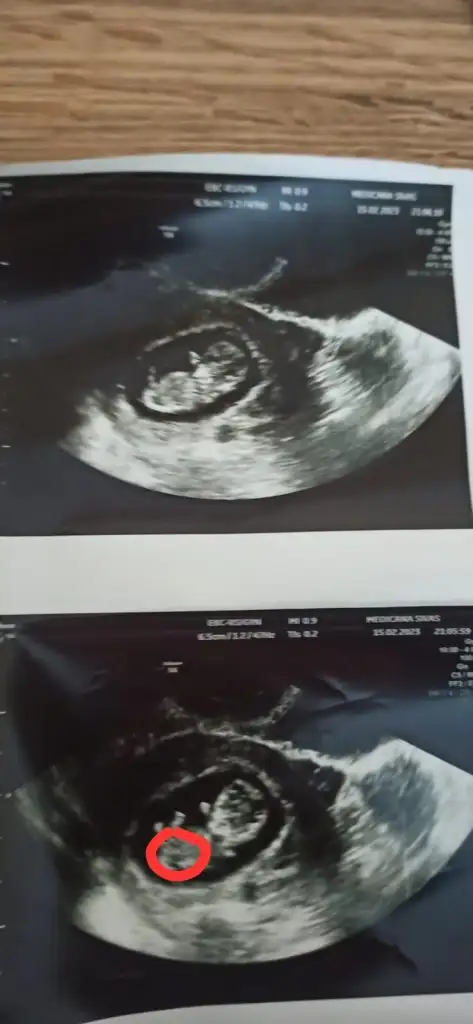

Maşallah diyelim öncelikle içimden kız geçtiKizlar 13+1 deyim bana da cinsiyet tahmininde bulunurmusunuz

Eki Görüntüle 3214911 Eki Görüntüle 3214912